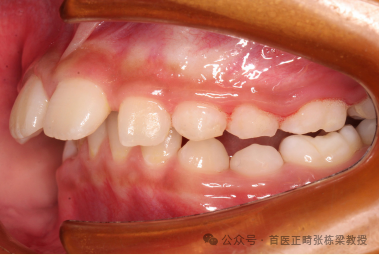

像这位9岁小朋友嘴凸、下巴后缩早期矫正改善效果也是不错的。

孩子存在的问题:骨性II类牙性 II 类 1 分类,下颌后缩,上前牙严重唇倾,深覆合,极度深覆盖,上牙弓狭窄。

早期矫正方案:上颌垫固定扩弓器,慢速扩弓,佩戴一个月后,当孩子上颌牙弓宽度到位后,后牙覆合覆盖充分后,就拆掉扩弓器。辅助生物调节器,让孩子弹舌训练每日 500 次,辅助维持上颌牙弓宽度。

后续增加佩戴口外弓,每天至少 12 小时,为期半年多时间,孩子下颌位置稳定,下颌生长发育限制解除,潜力释放,停戴矫治器,定期复诊,监测孩子后续生长发育。